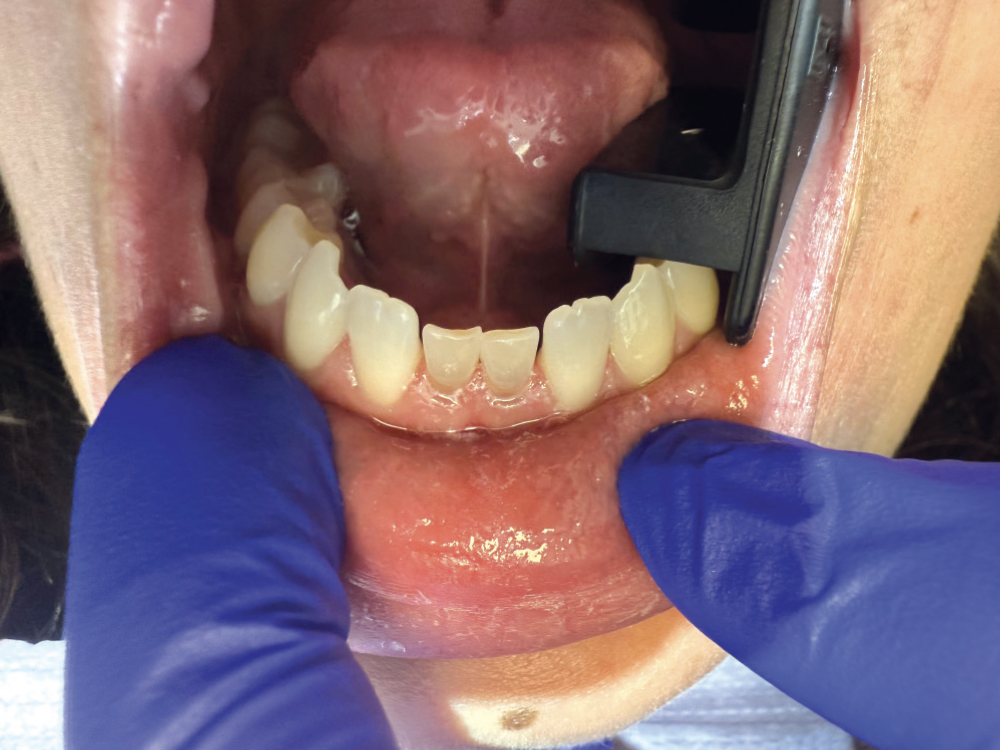

Recently, I had a young patient with two retained primary incisors on the lower arch — small, gray and highly visible. She had been quoted over $10,000 for implants elsewhere, which wasn’t feasible for her. I offered a same-day solution using milled composite crowns. We prepped conservatively, milled two units with CAMouflage® NOW Milling Blocks in under 15 minutes, and delivered them that hour. The transformation was stunning — and the experience was life-changing for her. She told me later that she originally didn’t believe me when I said we could fix it in one appointment. Seeing her smile without hesitation was a moment I won’t forget.

Before Crowns

After Crowns

Retained primary teeth O and P were crowned with composite crowns milled out of CAMouflage® NOW Milling Blocks in about 7 minutes. In less than an hour, this patient was able to smile like never before.